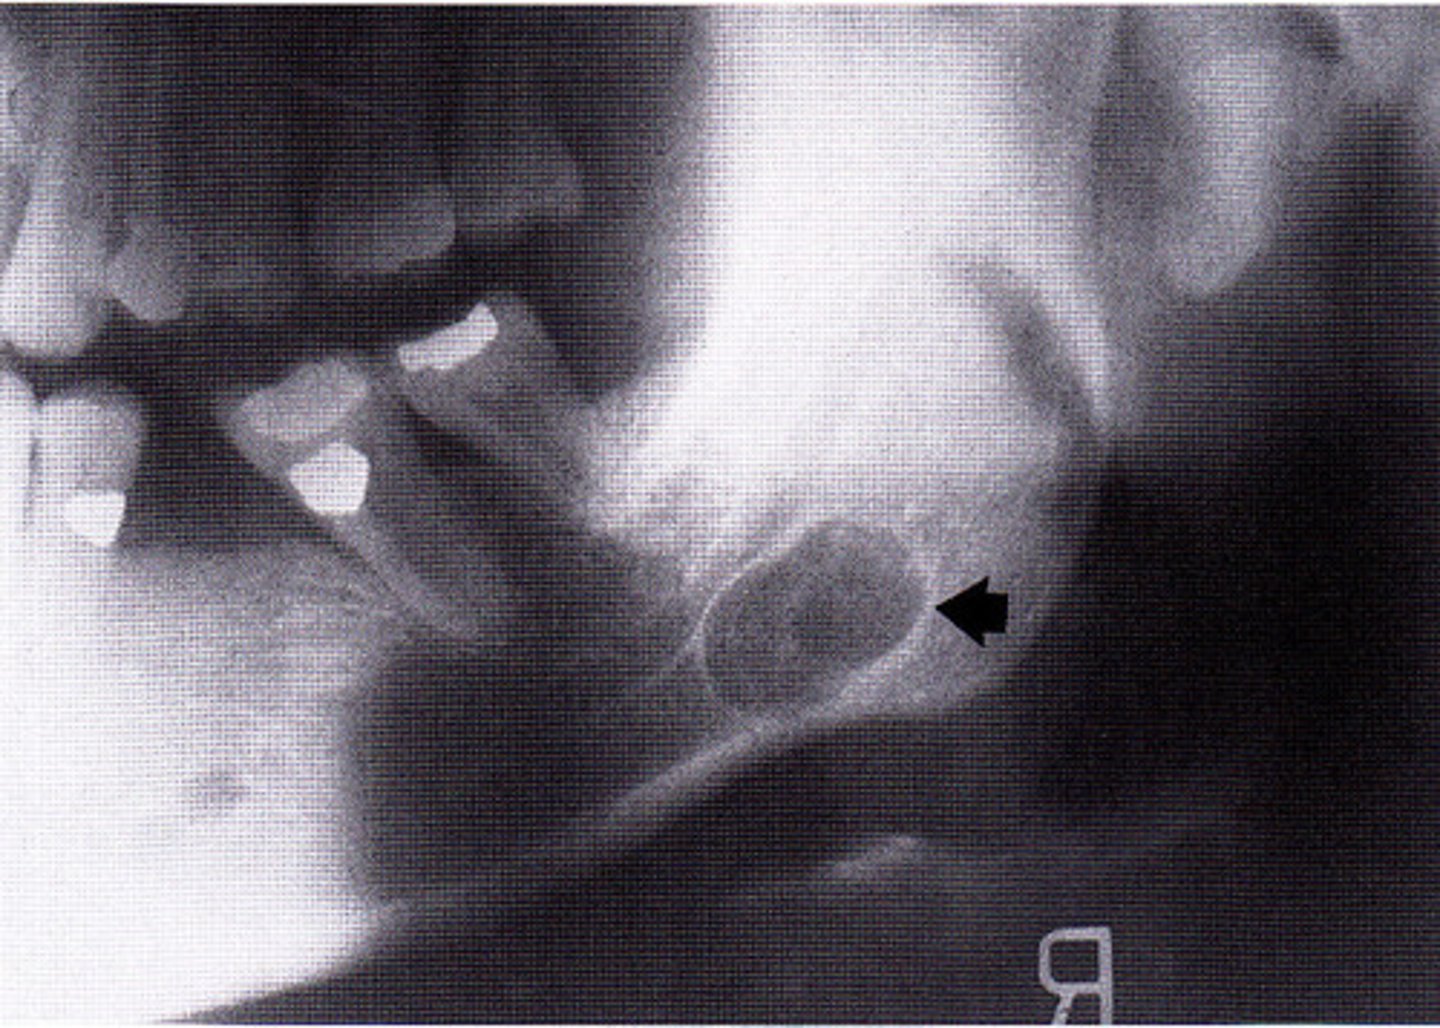

What are radiographic features of stafne bone cysts?

well-defined cyst-like radiolucency

1. anterior to angle of mand & inferior to mandibular canal

• unilateral or bilateral

radiolucent intraosseous lesion that is NOT lined with epitheium = NOT A TRUE CYST! **KNOW for exam

• also called Static Bone Cyst and Stafne Defect

developmental concavity containing normal salivary tissue on lingual aspect of posterior mandible

**KNOW FOR EXAM